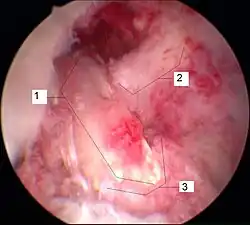

Arthroscopie diagnostique

La sécurité diagnostique la meilleure est obtenue par arthroscopie diagnostique. Ce procédé représente l'étalon-or pour le diagnostic de la rupture de LC. Ce procédé relève d'une chirurgie invasive au minimum, mais comporte certains risques, comme toute intervention chirurgicale dans le genou du patient[118]. Comme cependant le traitement chirurgical d'une rupture de LC sera conduit par chirurgie arthroscopique, il est possible d'enchaîner celle-ci immédiatement après l'arthroscopie diagnostique, par la résection partielle du ligament (pour une déchirure) ou la reconstruction en cas d'arrachement. Avec l'accroissement de la facilité de l'IRM, le nombre d'arthroscopies purement diagnostiques a nettement diminué ces dernières années[119],[120]. L'arthroscopie diagnostique est quand même utilisée comme précédemment comme procédé de choix pour une compréhension certaine du diagnostic de rupture de LC, en cas d'examen clinique confus et d'IRM difficile à interpréter[118].